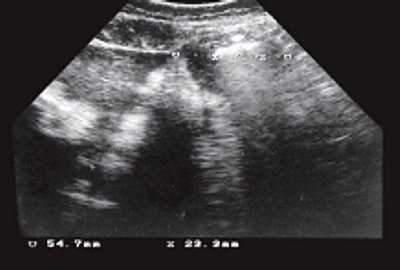

При ультразвуковом исследовании (УЗИ) выявлен плод мужского пола, все основные размеры которого соответствуют 34-35 неделям беременности. В желчном пузыре плода определялось (рис. 1) множество эхоплотных включений, дистальнее которых определяются нечеткие акустические тени, полностью заполняющих просвет. С подозрением на желчнокаменную болезнь плода больная была направлена в Республиканскую клиническую больницу N1 г. Чебоксары для дальнейшего ведения беременности, где повторное исследование не проводилось. Там же произошли срочные роды - на фоне ОПГ-гестоза, анемии, трихомониаза родился доношенный мальчик.

Рис. 1. Поперечное и косое сечение через туловище плода (по длиннику и поперечнику желчного пузыря). Метками обозначен желчный пузырь.

При УЗИ новорожденного в желчном пузыре определялись крупные эхопозитивные структуры, полностью занимающие просвет желчного пузыря. Ребенок был выписан из больницы с клиническим диагнозом: гипоксически-травматическое поражение центральной нервной системы, синдром гипервозбудимости, миотонический синдром, натальная травма шейного отдела позвоночника, конъюгационная желтуха, желчнокаменная болезнь (конкременты желчного пузыря), внутриутробная инфекция, омфалит, флебит пупочных сосудов. Было рекомендовано диспансерное наблюдение, повторное УЗИ через 6 месяцев с последующим решением о возможном хирургическом лечении желчнокаменной болезни.

Желчнокаменная болезнь - заболевание, характеризующееся образованием конкрементов в просвете желчевыводящей системы, вследствие различных факторов, чаще всего это: нарушение обмена желчных кислот (в результате образуются холестериновые и пигментные конкременты), инфекционно-воспалительные заболевания (смешанные конкременты) и стаз (билирубино-известковые конкременты). В описанном случае скорее всего имеет место сочетание инфекции и нарушение обмена, что привело к образованию "мягких" камней. Интересной особенностью случая, по мнению автора, является редкость выявления данной патологии плода [3,4].